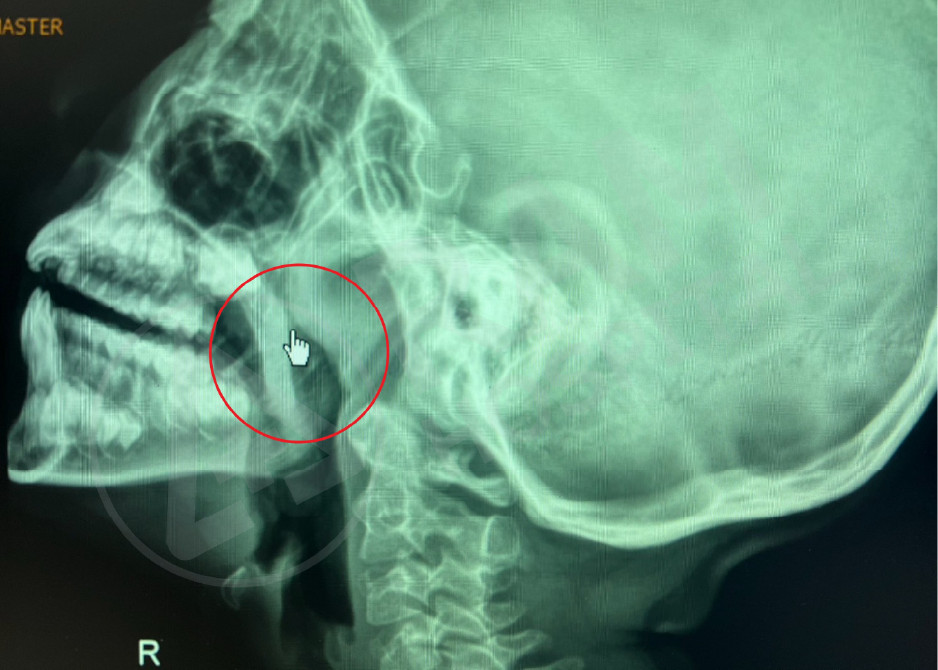

术前

真实案例

术后

Source: Photo courtesy of Dr. Puripan Aramawattanapong, Ear, Nose, and Throat Specialist